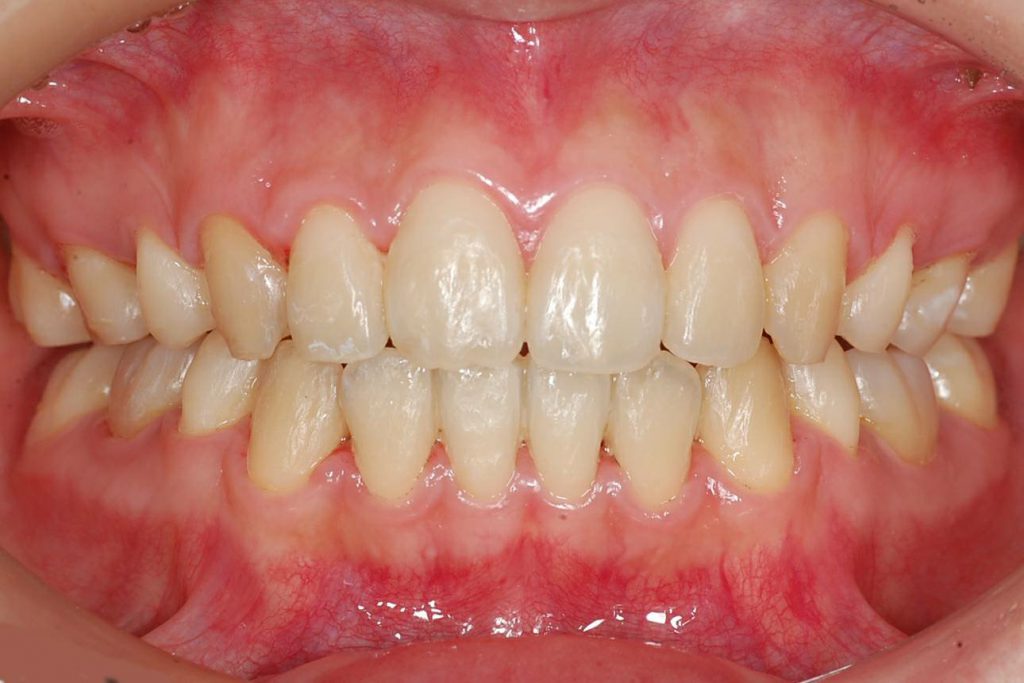

永久歯列期の全体的な治療では、機能的にも審美的にも良好な永久歯咬合の確立を目指します。この時期には、一般的にワイヤー装置を使うことが多いです。

永久歯列期の全体的な治療の方針は、非抜歯によるもの、抜歯を併用するもの、外科手術を併用するものの3つに分けられます。全ての患者さんに対して、抜歯せず、手術せず、良質な矯正歯科治療を提供したいという想いは矯正医にとって共通です。しかし、骨格的な不正や、歯と歯槽骨の不調和が顕著な場合には、抜歯や外科手術を併用しないと治療が難しい場合があります。